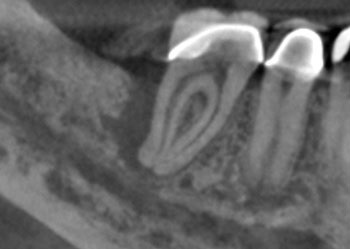

Fig. 3: Recall PA.

The patient returned in three months, when resolution of symptoms, healing of the deep probing defect and bone regeneration were confirmed. The tooth was obturated, and a foundational restoration was placed before the rubber dam was removed. Fourteen years of follow-up confirmed long-term periradicular health. The amount of appreciation and gratitude that this patient expressed reminds us that each individual tooth demands our best efforts.